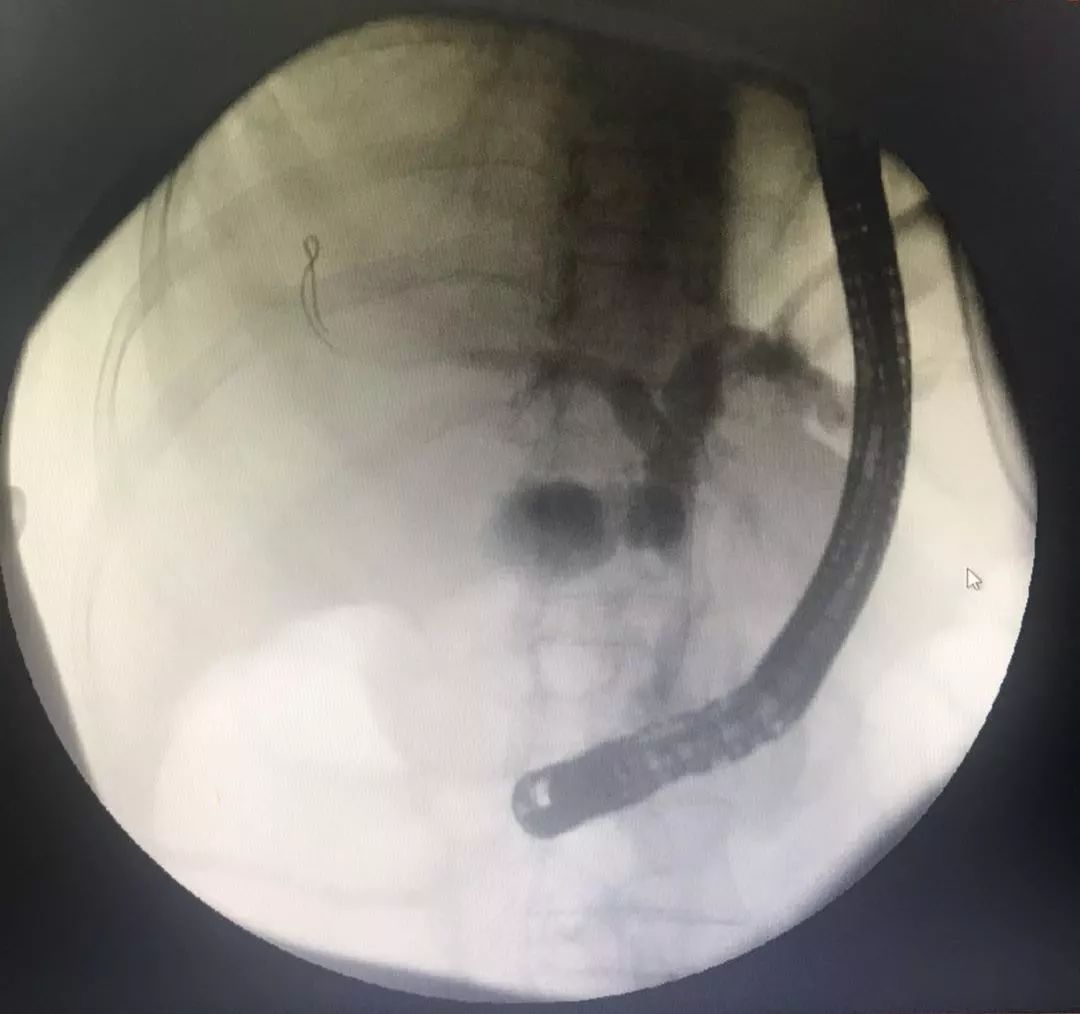

造影示:胆总管上段梗阻

沿11点方向切开十二指肠乳头约0.3 cm,见墨绿色胆汁涌出。保留导丝,经导丝置入一8mm×60 mm无覆膜胆道金属支架,支架下端位于乳头开口下方1.0 cm处,支架上端过狭窄段约2cm,见有大量脓性胆汁涌出。内镜操作顺利,麻醉满意,未出现出血,穿孔、胰腺炎等并发症。

内镜示:肠内支架引流脓性胆汁

造影示:支架位置良好